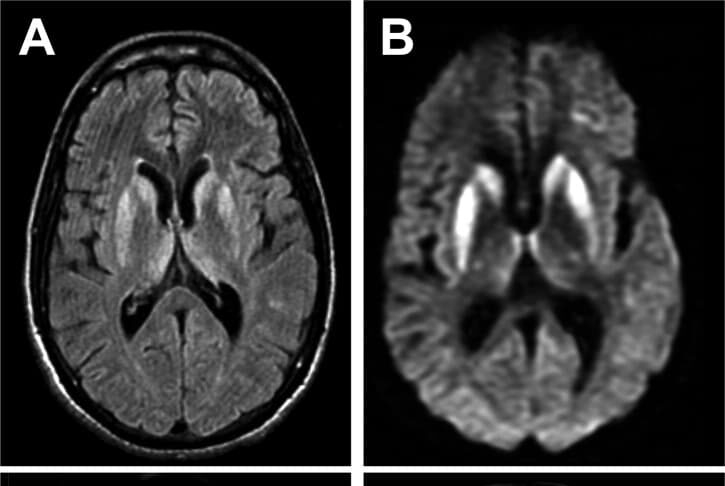

4Creutzfeldt-Jakob

What is it?

This is a very rare disease that causes fatal brain disorders, and it is incurable because the treatment is under research.

What causes it?

The disease is caused by an abnormal infectious protein in the brain called Prion. It also leads to heart failure, pneumonia, or respiratory failure. Generally, the patients who suffer from this disease can live only about 12-14 months after the symptoms appear.

What are its symptoms?

The symptoms begin with immediate sickness, personality changes, difficulties in walking or balancing, then falling into a coma before death.